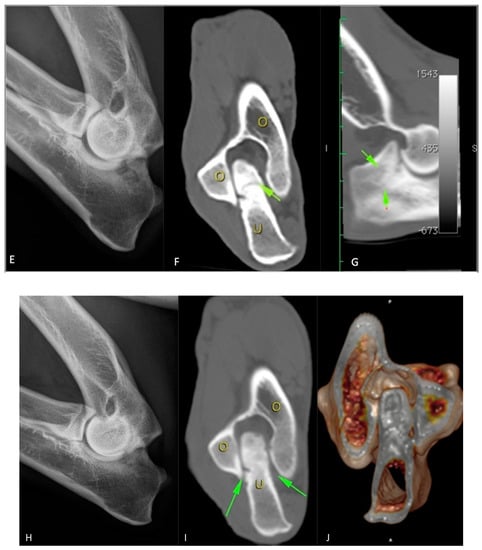

The healing area appeared to be slightly radiolucent as compared with the surrounding bone. In Figure 4, it is possible to observe the presence of newly formed bone tissue (blue arrow) crossed by numerous vascular channels of variable amplitude and irregular course which often flow together. Within this area, a calcified cartilage residue invaded by vascular structures is still recognisable. It appears to be more radiopaque and provides evidence of secondary healing consisting of endochondral ossification. Bypassing this region, more internally along the conjunction area, the bone tissue appears to be more regular, and the arrangement of the vascular channels follows a radial course (Figure 4).

Figure 4.

Microradiograph of bone tissue taken from the anconeal process.

The single case in which the microradiographic assessment was performed demonstrated a clear osteoinductive effect of the treatment with endochondral ossification and regular bone formation.